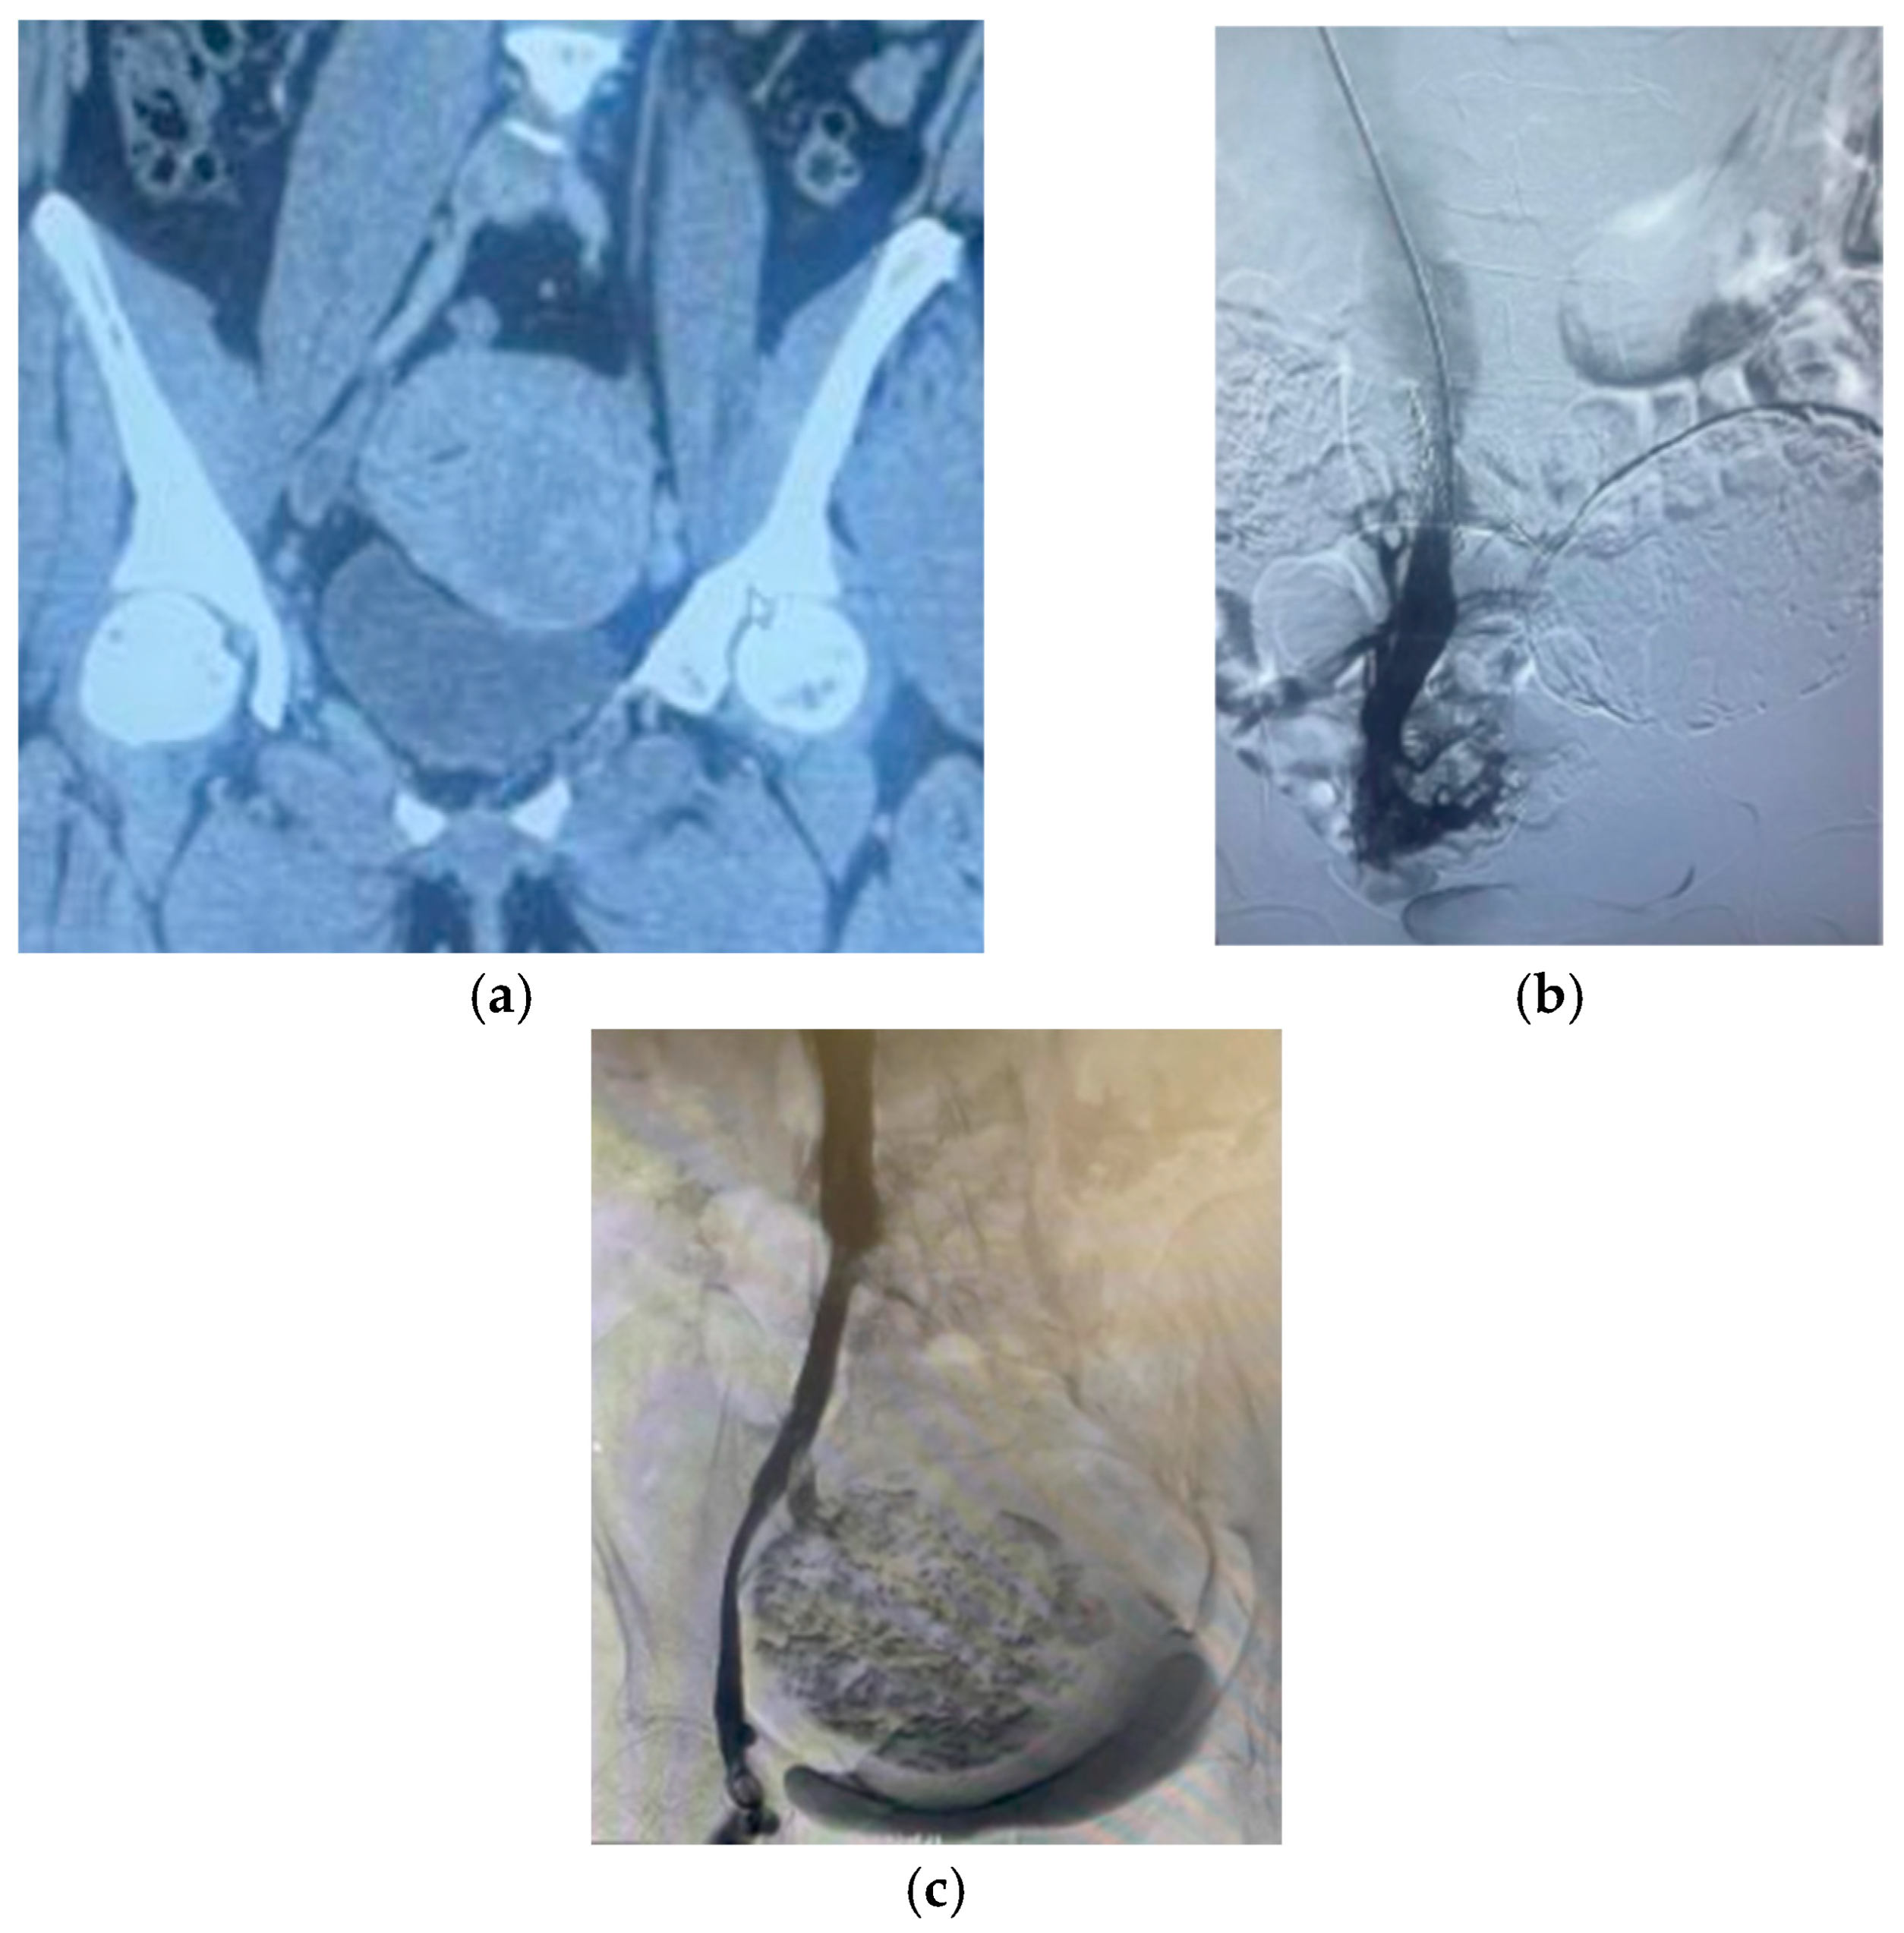

- Serena, T.; Bailey, W.; Bendix, S. Endovascular management of extensive iliocaval thrombosis secondary to synchronous uterine myoma compression and May-Thurner syndrome. J. Vasc. Surg. Cases Innov. Tech. 2022, 8, 179–182. [Google Scholar] [CrossRef]

- Barnaby, J.; Martynov, A.; Shah, S.; Ramanathan, A. Giant subserosal myoma causing deep venous thrombosis in a patient with pre-existing May-Thurner syndrome. Radiol. Case Rep. 2020, 15, 644–649. [Google Scholar] [CrossRef] [PubMed]

- Zhang, H.; Li, H.; Chan, Y.; Cui, D.; Cheng, S. Multidisciplinary staged management of iliofemoral venous thrombosis caused by huge uterine fibroid: A case report. Hong Kong Med. J. 2021, 27, 46–49. [Google Scholar] [CrossRef] [PubMed]